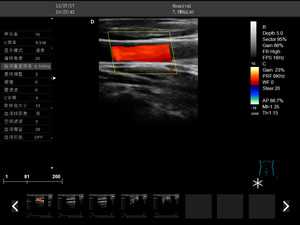

彩色多普勒

全數字成像技術

1.電影/圖像回放功能

2.彩色多普勒速度模式

3.能量多普勒模式

4.方向彩色能量多普勒模式

5.脈沖頻譜多普勒模式

6.三同步模式

7.分屏實時顯示模式